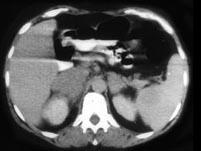

问题 男,65岁,腋下触及肿大包块,全身浅表淋巴结肿大,请结合所提供图像,选择最佳答案 ( )

选项 A、双侧肾上腺转移瘤 B、肾上腺癌 C、双侧肾上腺增生 D、双侧肾上腺淋巴瘤 E、双侧肾上腺腺瘤

答案 D